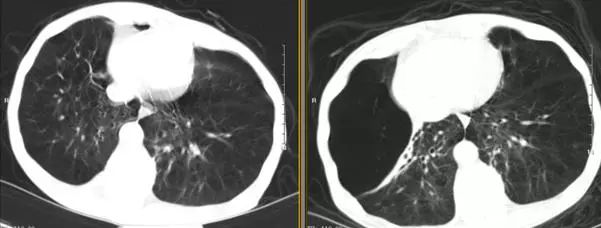

术后5天胸部CT(图7)显示右肺上叶局灶性气胸,肺大疱明显缩小,中叶未能复张,血气分析(鼻导管吸氧2L/min)提示:PH 7.425,PaO261.8 mmHg,PaCO246.8 mmHg,HCO3 -30.0 mmol/L,遂出院观察。住院期间无院内获得性肺炎、咯血、单向活瓣移位等并发症。

图7 术前2天(右)与术后5天(左)胸部CT对比